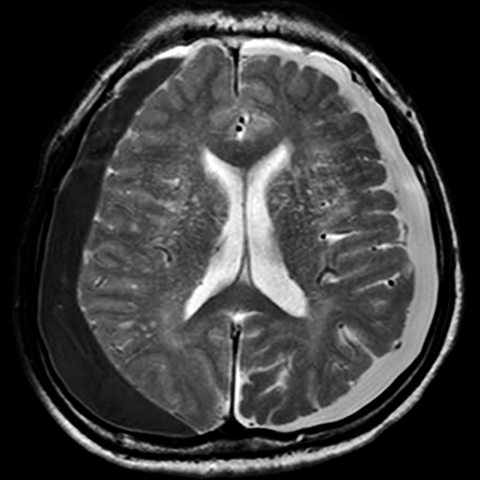

55 year old female presents to the emergency room after a car accident [4 of 4]